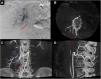

La «Cone-Beam computed tomography» (CBCT) o tomografía computarizada de haz cónico obtiene imágenes tridimensionales mediante un detector bidimensional. Su aplicación en la planificación y evaluación de los procedimientos mínimamente invasivos guiados por imagen, puede mejorar tanto la seguridad como la eficacia de intervenciones vasculares y percutáneas. El objetivo de este manuscrito es hacer una revisión de las consideraciones técnicas, de las principales aplicaciones clínicas y direcciones futuras de la CBCT en radiología vascular e intervencionista y en neurorradiología intervencionista.

Cone-Beam computed tomography (CBCT) obtains three-dimensional images using a two-dimensional detector. The use of CBCT in treatment planning and evaluation increases the safety and efficacy of minimally invasive procedures. This article reviews the technical considerations, main clinical applications, and future directions of CBCT in vascular and interventional radiology and interventional neuroradiology.